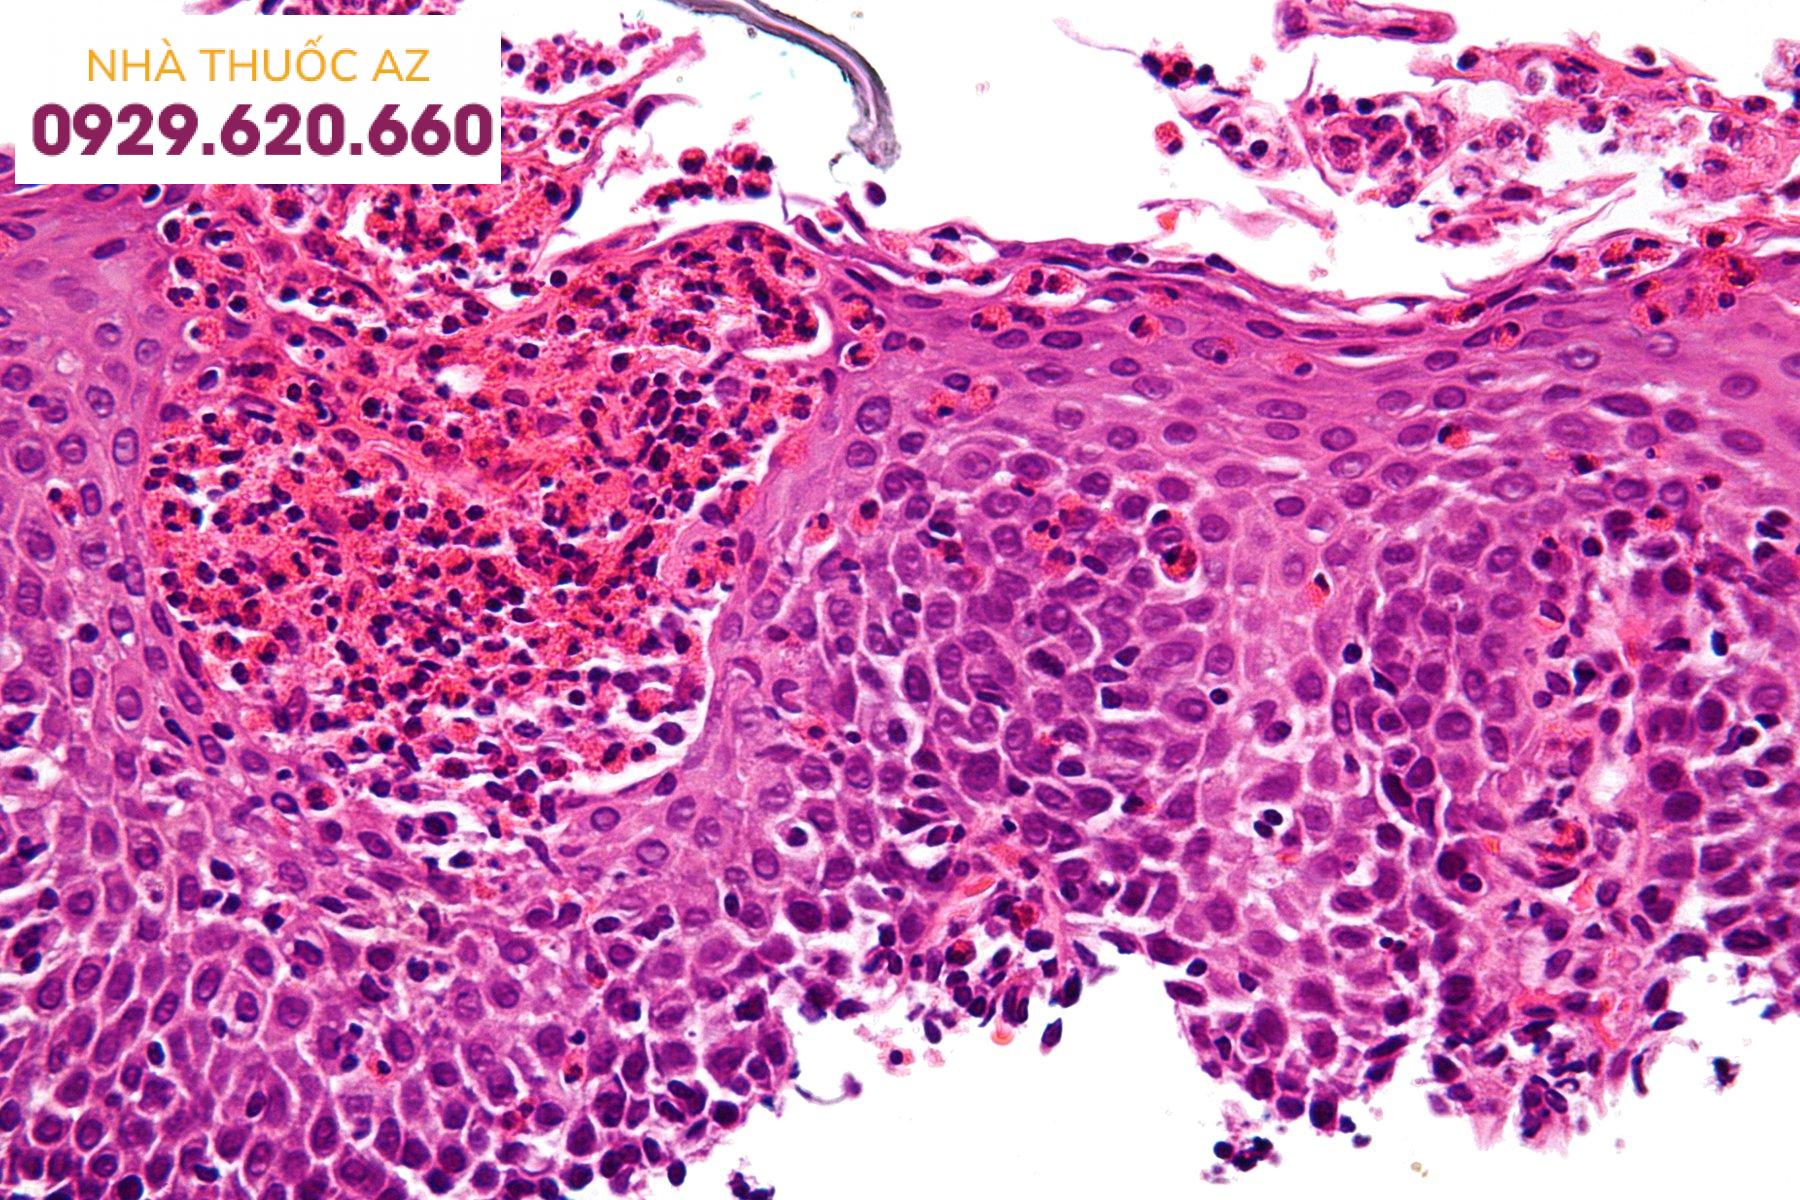

Mặc dù sự phục hồi của hàng rào biểu mô thực quản là giả thuyết được chấp nhận nhiều nhất đối với giải thích sự tồn tại của PPI-REE, nghiên cứu đầu tiên giải quyết vấn đề này một cách khách quan ở EoE vừa được công bố gần đây. Mười sáu bệnh nhân có bạch cầu ái toan thực quản> 15 bạch cầu ái toan/ quang trường được so sánh với mười một bệnh nhân đối chứng lúc ban đầu. Tính toàn vẹn của niêm mạc thực quản được đo ở thực quản xa, phương pháp đánh giá là dùng đầu dò phổ có kháng trở mô trong quá trình nội soi và xem xét mô bệnh học: 2 mẫu sinh thiết được lấy qua nội soi để phân tích bằng kính hiển vi điện tử về tiêu chuẩn tăng khoảng cách khoảng gian bào và 4 mẫu sinh thiết để đo điện trở xuyên biểu mô và thông lượng xuyên niêm mạc của các phân tử được đánh dấu huỳnh quang có kích thước 0,3 và 40 kDa (tương tự như kích thước của chất gây dị ứng thực phẩm).

Ở bệnh nhân tăng bạch cầu ái toan thực quản, tất cả các phép đo về tính toàn vẹn của niêm mạc đều bị suy giảm đáng kể khi so sánh với các đối chứng. Bệnh nhân thực quản tăng bạch cầu ái toan sau đó được cho dùng omeprazole 40 mg hai lần hàng ngày và được đánh giá lại 8 tuần sau đó. Sau liệu pháp ức chế axit, tính toàn vẹn của niêm mạc đã được khôi phục một phần ở PPI-REE, nhưng không xảy ra ở bệnh nhân EoE. Các tác giả kết luận rằng sự suy giảm tính toàn vẹn của niêm mạc trong PPI-REE có thể là do GERD, trong khi nó có thể liên quan đến tuyển dụng tế bào viêm trong EoE. Do đó, điều này nghiên cứu cho thấy rằng sự tiếp xúc của biểu mô thực quản có axit trào ngược ở bệnh nhân PPI-REE, do biểu mô suy giảm hàng rào, có thể là “tác động” đầu tiên trong sự phát triển của bạch cầu ái toan thực quản.